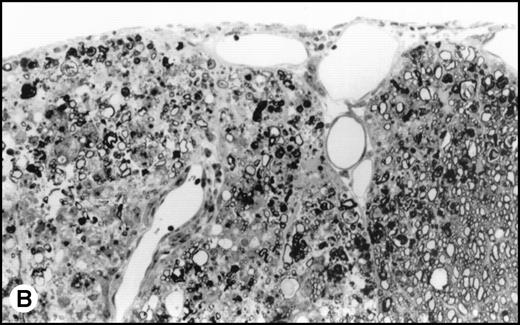

(A) Histology of SJL/J spinal cords from mice infected with TMEV. Section of spinal cord of an SJL/J mouse, 130 days after infection with TMEV. The right anterior column is completely demyelinated and numerous large lipid-laden macrophages are present close to the central sulcus. The gray uniform background reflects conspicuous gliosis in the demyelinated area (1-μm–thick, Epon-embedded section, stained with toluidine blue; original magnification × 220). (B) Section from spinal cord of an SJL/J mouse 130 days after infection with TMEV and after treatment with radiation and BMT. Inflammatory cells are still around the large venule in the parenchyma of the left anterior column, indicating active disease, but many axons are still surrounded by myelin sheaths and gliosis is less prominent (1-μm–thick, Epon-embedded section, stained with toluidine blue; original magnification × 220).